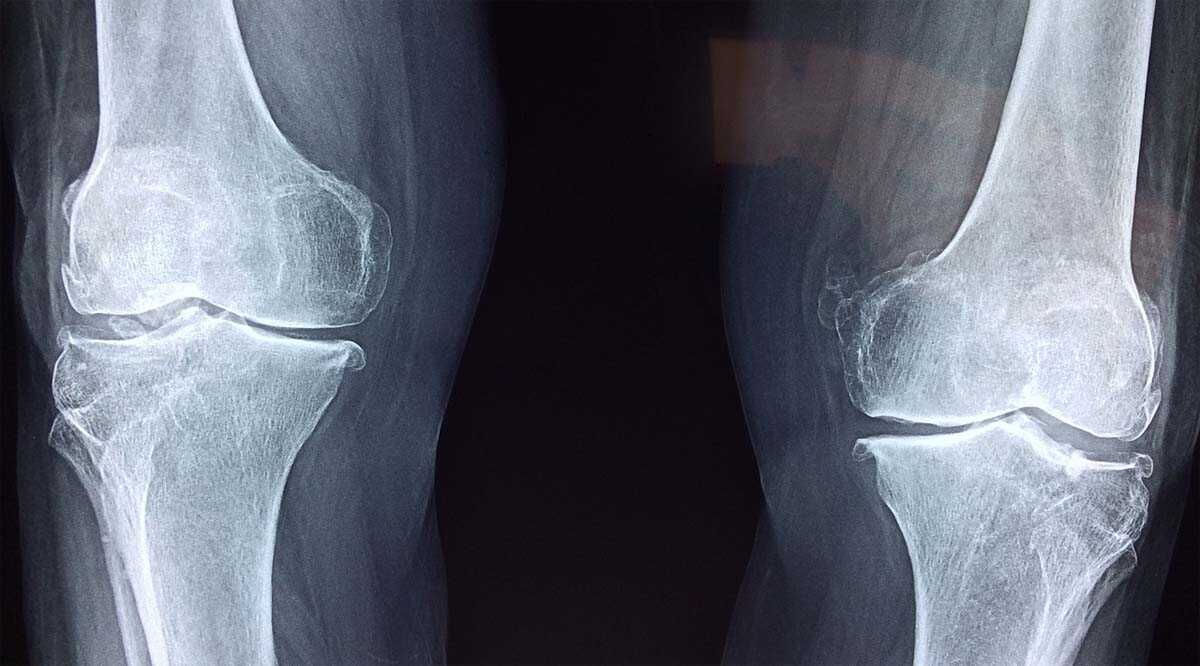

Pengapuran tulang, atau dikenal dengan istilah medis osteoporosis, merupakan kondisi di mana tulang menjadi rapuh dan keropos. Kondisi ini dapat menyebabkan rasa sakit, kaku sendi, dan bahkan patah tulang.

- Lakukan Pemeriksaan Rutin

Pemeriksaan rutin dapat membantu mendeteksi pengapuran tulang sejak dini, sehingga dapat diobati dengan tepat.